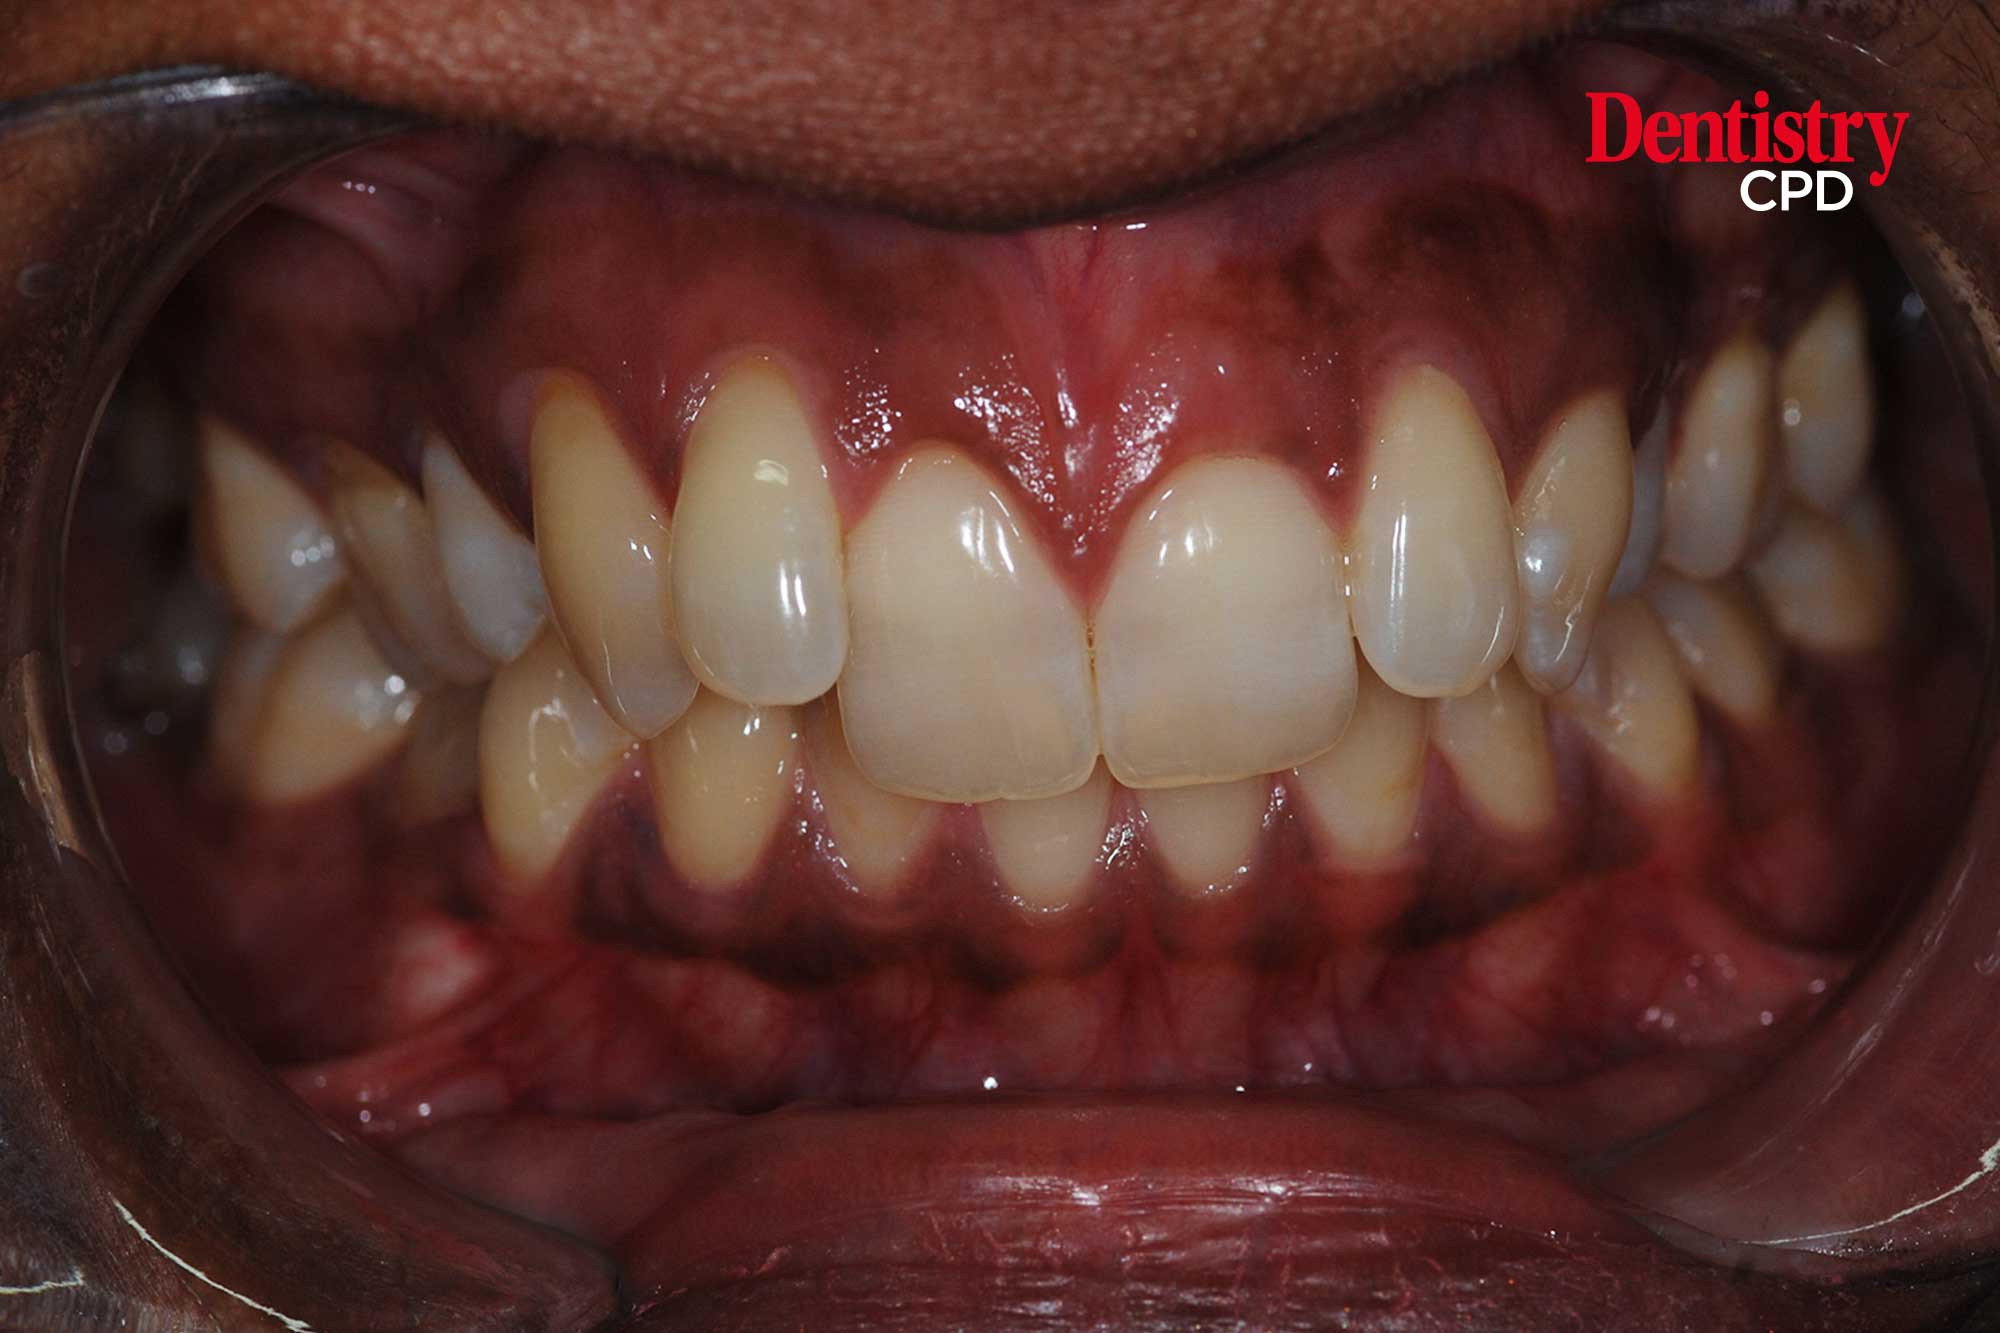

Chaw-Su Kyi describes treatment in a patient with severe orthodontic relapse of both arches.